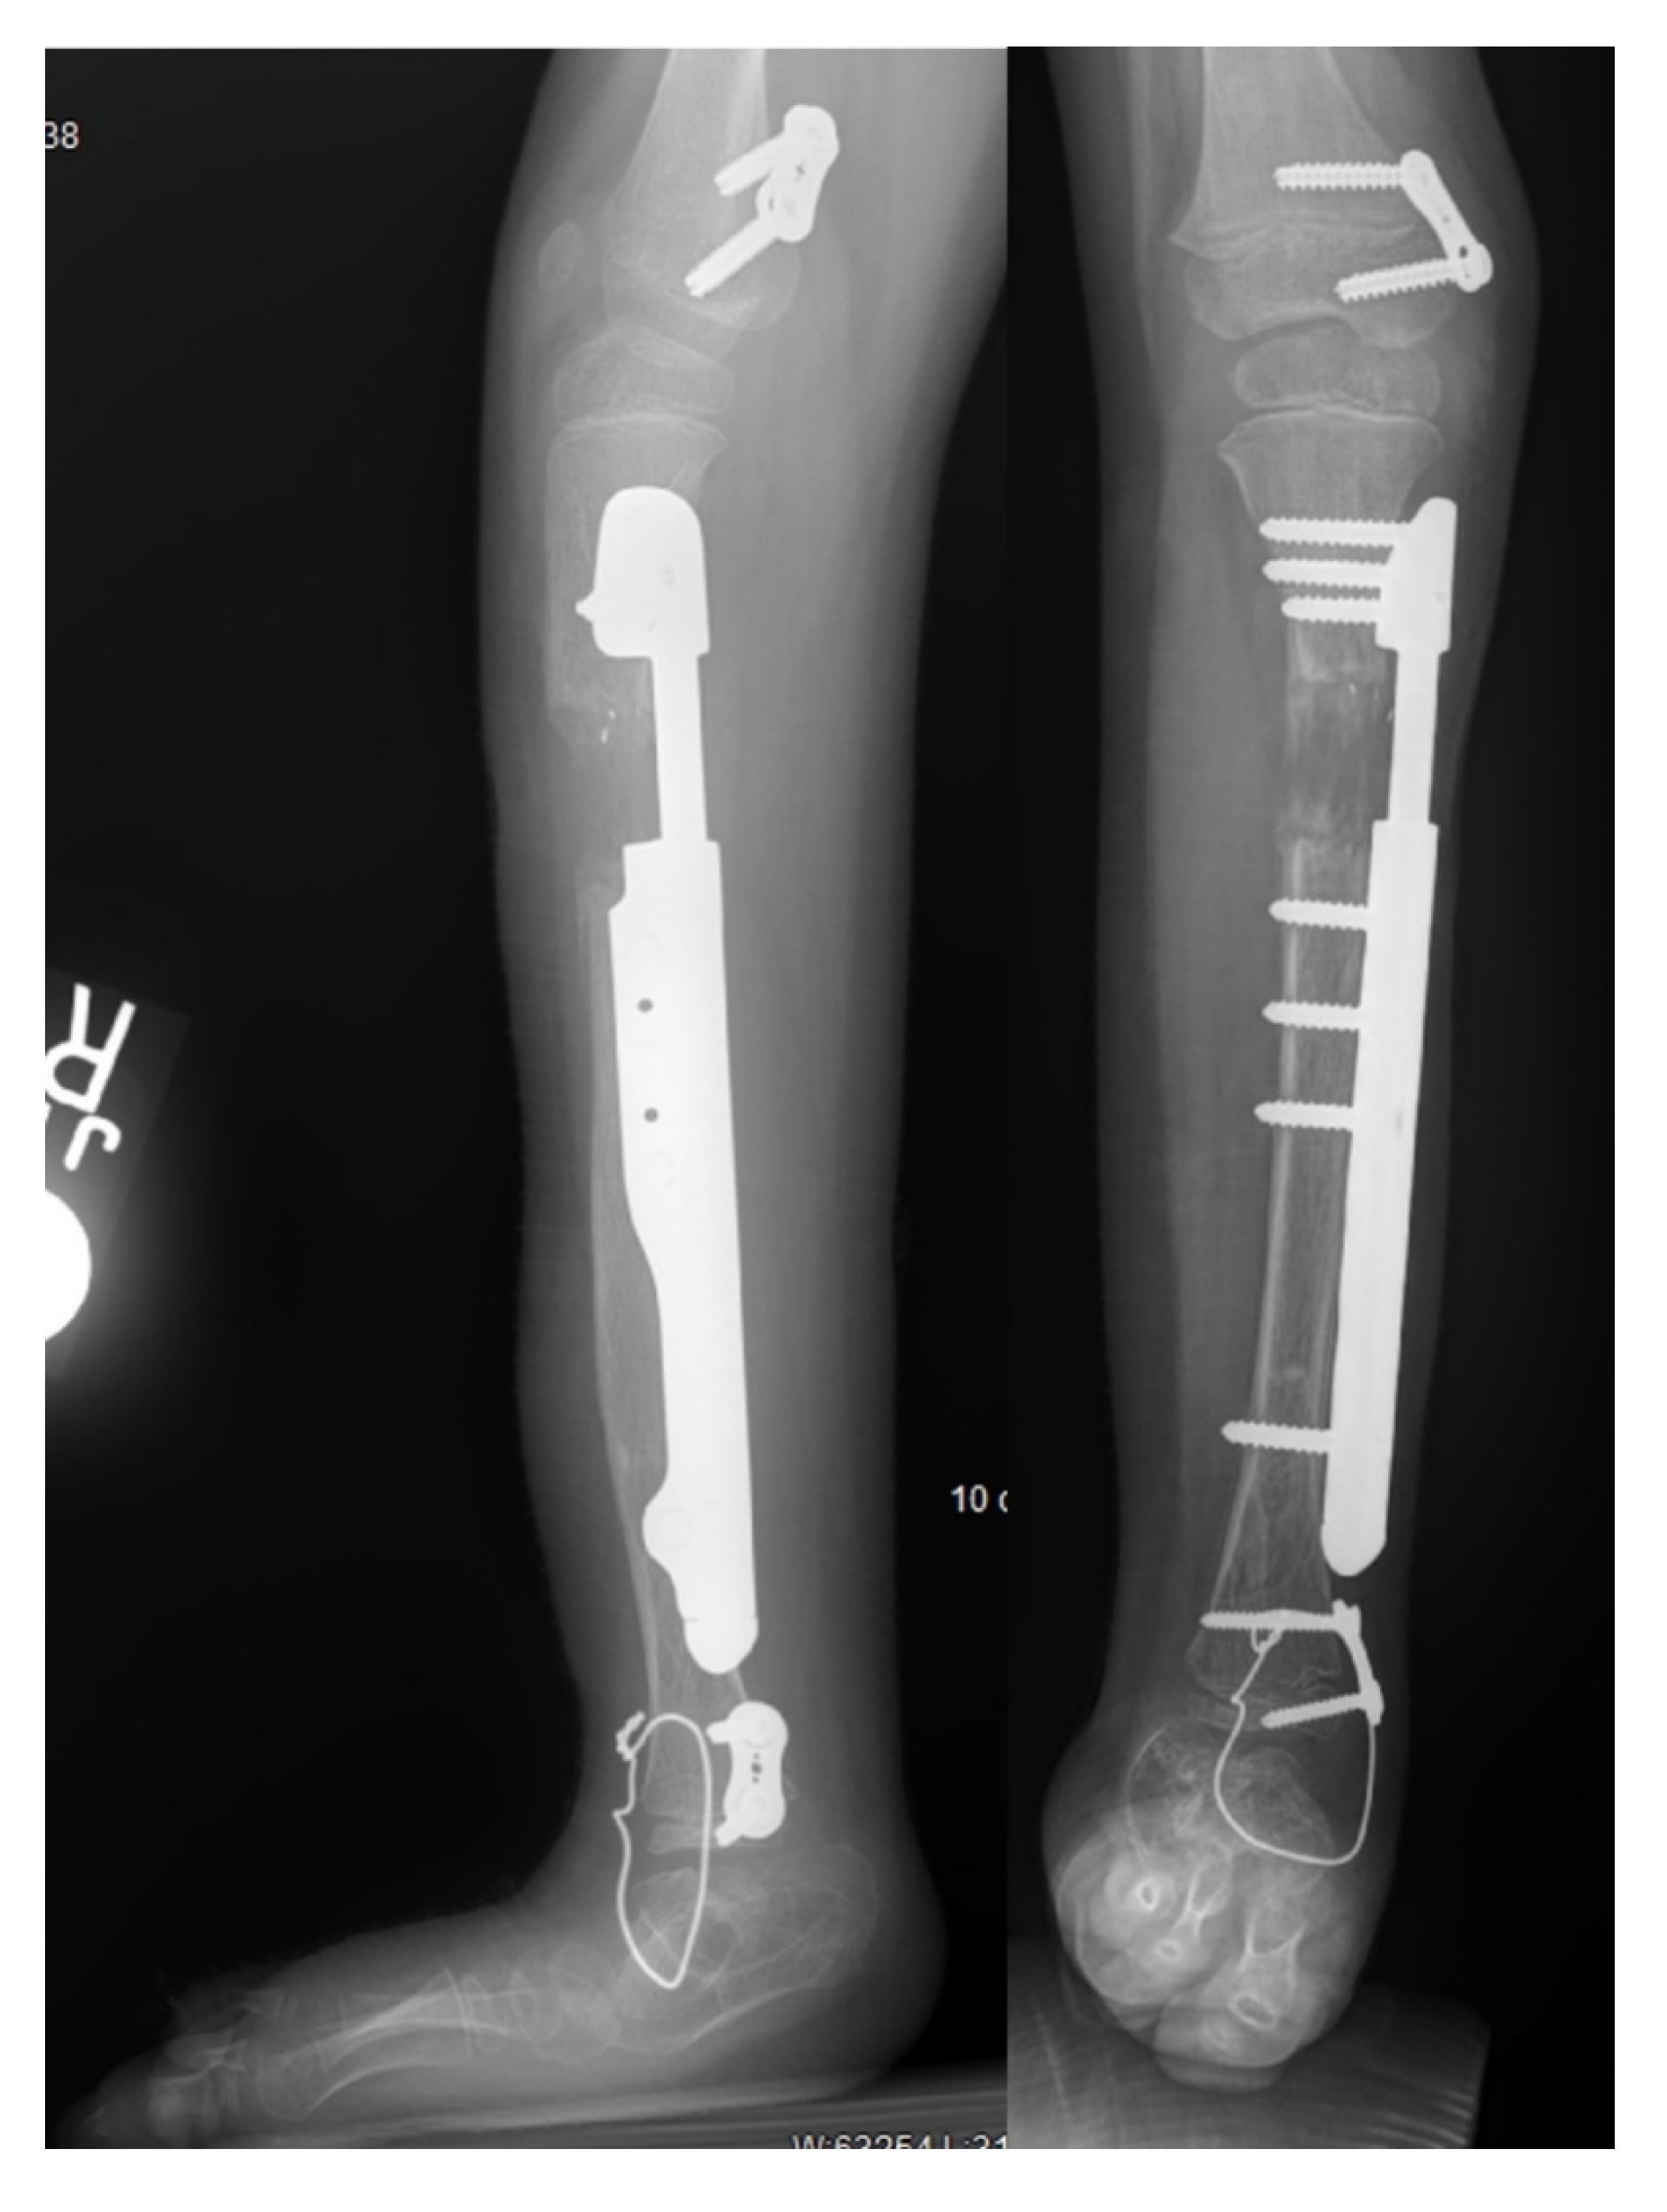

With the recent advancement of internal lengthening devices, there is a trend to perform lengthenings internally if possible. External fixators still play an important role in tibia lengthening, especially in young children where physeal and bone diameter or length prevent insertion of a rigid nail. All-internal lengthening, with an extramedullary implant position is an emerging option in patients who would traditionally require an external fixator for lengthening in the femur and tibia. Extramedullary implantable limb lengthening (EMILL) is a new technique, first performed by the senior author in 2015 [32], that uses an implantable nail attached to the bone like an internal-external fixator. EMILL has been shown to be a safe technique to lengthen the femur or tibia in patients in which an external fixator would otherwise be necessary [32,33,34]. There were 4 patients who underwent EMILL for tibial lengthening reported by Shannon et al. [34]. None had axial deviation. One had a locking screw breakage and one had a screw head erode through the thin skin on the medial side of the leg. Although there were no reported axial deviations, the authors have subsequently had cases of axial deviation with tibial EMILL (Figure 7). The senior author, in collaboration with Nuvasive Specialized Orthopedics has continued the evolution of the Precice mechanism to develop an implantable limb lengthening plate called the Precice plate. The Precice plate device was specifically designed for EMILL and has now was cleared by the FDA in December of 2019 (Figure 9). It has been used by the authors in 20 cases and will be the subject of a future report. A lengthening plate further expands the indications for EMILL and the ability to utilize implantable lengthening for younger children [35].

Figure 9.

AP and lateral radiographs of a 4-year-old girl who had a previous SUPERankle procedure and one 5 cm lengthening with an external fixator. She had a Precice plate applied to the medial side of the tibia. To prevent equinus the foot was tethered anteriorly with a temporary arthrodesis wire. The Precice plate (Nuvasive Specialized Orthopedics, Aliso Viejo, CA, USA) can lengthen up to 4.5 cm.

Lengthening of the tibia with an all-internal technique does carry additional risks of developing an equinus contracture compared to lengthening with an external fixator in FH. External fixators can be applied across the ankle to incorporate the foot, thus allowing control of the foot and ankle during lengthening to prevent equinus. All patients undergoing internal tibial lengthening are required to use ankle-foot orthosis when sitting or lying around and undergo daily physical therapy to prevent equinus. The lengthening goal in FH should be restricted to 5.0 cm or under and lengthened at a rate of 0.75 mm/day to avoid increased risk. In higher-risk tibial lengthenings, the senior author (D.P) developed a technique in 2003, inserting a temporary extraarticular ankle stabilization (EAAS) screw between the calcaneus and tibia to prevent equinus [36]. Inserting an extraarticular calcaneo-tibial screw is a safe and powerful technique that can be used in skeletally mature patients with FH to adequately maintain ankle dorsiflexion during the lengthening phase.